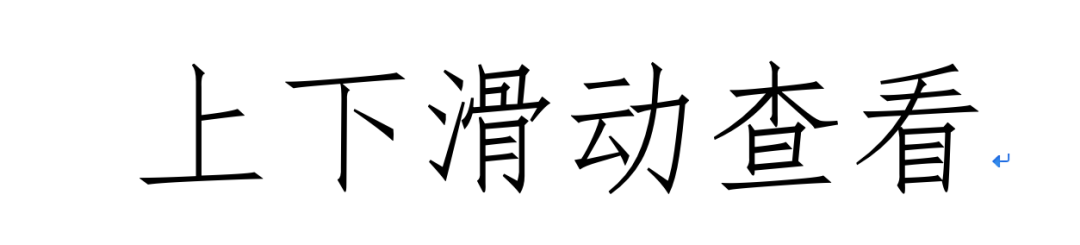

术中发现三角韧带深层矢状面撕裂

术中将骨折与韧带损伤一一处理。